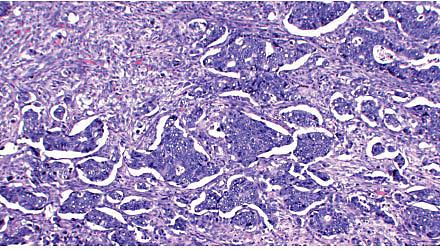

Screening for kolorektal cancer (KRC) blandt 50-74-årige i Danmark indledes i 2014. Dette sker blandt andet på baggrund af et gennemførlighedsstudium, der blev udført i Københavns og Vejle Amter i 2005-2006. I denne undersøgelse beskrives KRC i gennemførlighedsstudiets kohorte med henblik på effekt af screeningsdeltagelse på KRC-stadie og overlevelse. Screeningstesten bestod af en fæcesundersøgelse for ikkesynligt blod (FOBT) efterfulgt af kolo-skopi ved positiv test.

KRC i screeningskohorten i perioden 1.8.2005-31.12.2008 identificeredes ved hjælp af et udtræk fra Danish Colorectal Cancer Group’s (DCCG) database. Stadier fastlagdes på baggrund af patologisvar. Patienter i stadium 4 identificeredes via DCCG-udtræk, idet fjernmetastasering ikke altid verificeres histologisk. Patienter med rectumcancer blev inddelt i grupper med lokalt avanceret samt ikkeavanceret cancer. Oplysninger om evt. dødsdato blev indhentet fra CPR-registret i april 2013. Der blev udført overlevelsesberegninger med og uden korrektion for lead time.